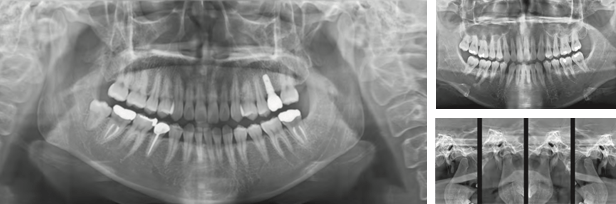

Panoramic

- 診療目的に合わせた多彩な撮影モード

- TMJ撮影、バイトウイング撮影、隣接面直行撮影など、目的に合わせて様々な撮影が可能です。

- Denosing(ノイズ除去)

- 被曝量を避けるためX線量を低下させるとノイズが増え画像の歪みが生じますがRAYSCAN独自のノイズ除去技術により画像の劣化を抑えています。

- 10段階のカスタマイズ画像フィルター

- ユーザーのお好みに合わせた画像フィルターを選択できます。

- AMF(Adaptive Moving Focus)

- RAYSCAN α(3D Edge)のセンサーは、独自のAMF技術によりノイズの少ないパノラマ画像を構成します

FMX View(デジタル切出し機能)

Panoramaから、様々なデンタル切り出しで見ること(保険適用)をサポートいたします。